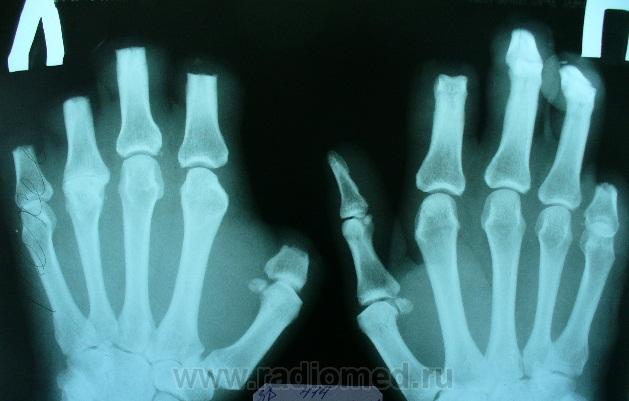

Ваши снимки, после обработки.

Снимки не узнать, как другим аппаратом снимали. Все-таки цифра - это...человек.

Лучше С.А. Рейнберга об отморожении и изменениях костей при этом не рассказать...вот один из фрагментов....

"Отсутствие параллелизма между клиническими и рентгенологическими проявлениями обморожений, т. е. несоответствие границ костных изменений, определяемых клиническими и рентгенологическими средствами, поднимает рентгенологическое исследование до уровня важного фактора выбора места и времени для оперативного вмешательства. Коллективный опыт показал, что без рентгенологического исследования хирургическое вмешательство (речь идет о некрозах кости) в принципе недопустимо, оно чревато неприятными последствиями и дальнейшими осложнениями; вследствие пренебрежения к рентгенологии производятся недостаточно радикальные операции, которые впоследствии неизбежно вынуждают прибегнуть к повторным вмешательствам. Действительные размеры костных поражений при обморожениях определяются главным образом рентгенологически; современный радикальный хирургический подход, имеющий целью излечение в короткие сроки, немыслим без рентгенологического контроля. Это доказано в диссертации А. В. Рязанской"